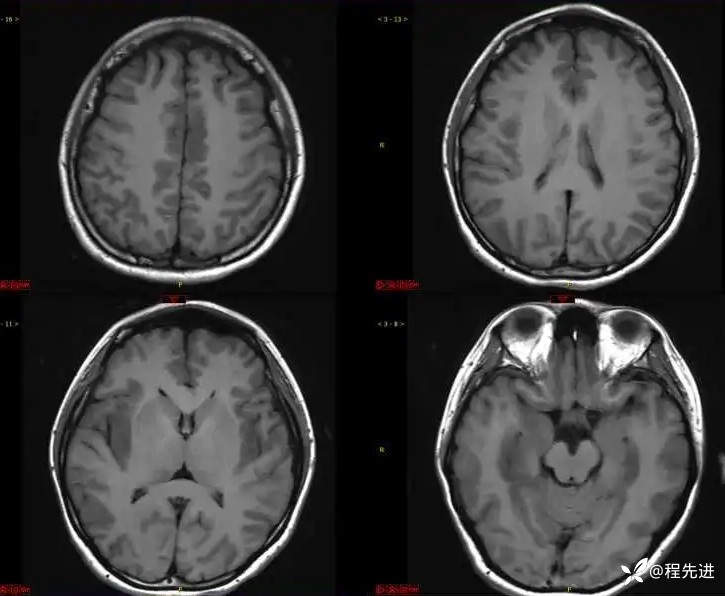

T1: